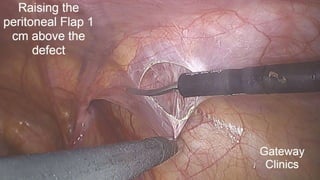

STEP 2: Creating the Peritoneal Flap

Incision of the peritoneum

The peritoneal incision starts 2 cm above the iliac spine/ 5cm above defect using the monopolar